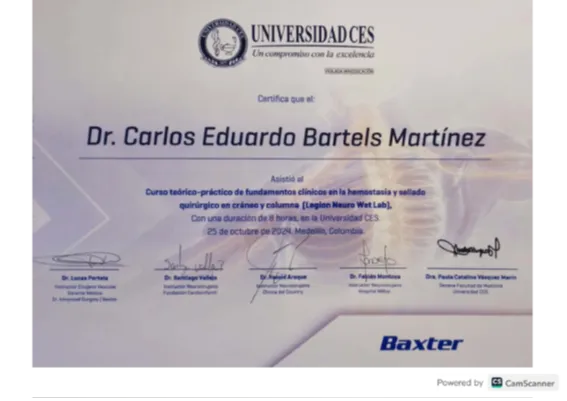

Conferences, Workshops & Continuing Education

- ✔️ Advanced trauma, neurocritical care, BLS/ACLS, and ATLS-style courses